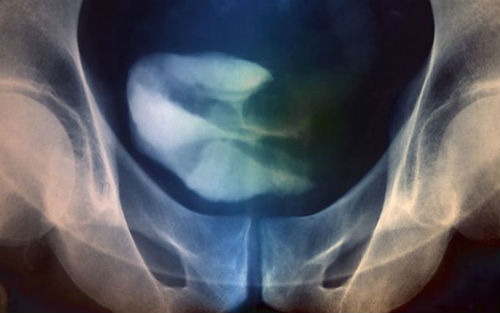

治疗6周后,43%的PD-L1阳性患者的肿瘤缩小了;12周后,比例上升到52%。在随后的治疗中,这些患者中有2人(7%)放射成像检测发现不再有癌症迹象。在PD-L1阴性患者中,也有11%的患者对治疗有积极的响应。